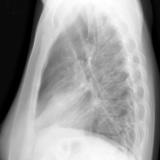

Case 1 Lateral

Date: 02/28/2004

Views: 3199